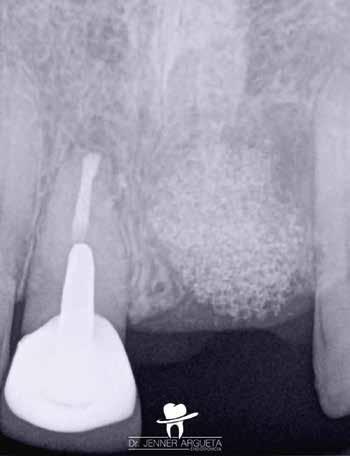

9. a–c. ábrák: A jobb felső nagymetszőfog (1.1) kezelése során készült radiológiai felvételek. Kiindulási röntgen: jól látható a gyökér-reszorpció és a gyökér oldalán elhelyezkedő radiolucens terület (a). A reszorpció szintjéig tartó munkahossz meghatározás (b). A gyökér-reszorpció ellátása kalcium-szilikát alapú anyag segítségével (c).

11. a–c. ábrák: A jobb felső nagymetszőfog (1.1) kezelése során készült radiológiai felvételek. Kiindulási röntgen: jól látható a gyökér-reszorpció és a gyökér oldalán elhelyezkedő radiolucens terület (a). A teljes munkahosszon levezetett mester poénról készült felvétel (b). Az endodonciai ellátás befejezését követően készített felvétel (c).

12. ábra: A jobb felső nagymetszőfog (1.1) kezelése során készült radiológiai felvételek. Kiindulási röntgen: jól látható a gyökér-reszorpció és a gyökér oldalán elhelyezkedő radiolucens terület (a). Az endodonciai ellátás befejezését követően készített felvétel (b). A hároméves kontroll alkalmával készített röntgenfelvétel a gyökér oldalán elhelyezkedő radiolucens terület teljes gyógyulását és a reszorpió megfelelő lezárását mutatta (c).

Esetbemutatás (4.)

Egy 35 éves férfi beteg a középső metszőfogait érintő érzékenység miatt kereste fel a rendelésünket. A klinikai vizsgálat során akut periapicalis abscessust észleltünk. A radiológiai vizsgálat eredményeinek kiértékelés során a jobb felső nagymetszőfog (11) gyökerét érintő reszorptív elváltozást láttunk. A beteg egy néhány évvel korábban bekövetkezett, a kérdéses régiót érintő traumás sérülésről számolt be. A diagnózisunk pulpa nekrózis és akut periapicalis abscessus volt.

A gyökérkezelés megkezdését követően az első ülésben nem lehetett a gyökércsatorna teljes munkahosszán végighaladni.

A gyökérkezelő tűk egy bizonyos mélység elérését követően folyamatosan a gyökér mezialis oldalán elhelyezkedő reszorbeálódott területbe vezették magukat. Emiatt a reszorpció által okozott defektus zárása mellett döntöttünk (9. a–c. ábrák). A

zárás során EQ-S eszközzel (Meta Biomed) szónikusan aktivált CeraSeal pasztát használtunk (10. ábra). A második ülés megkezdésére a reszorbeálódott területre helyezett anyag teljesen megkeményedett, és ezáltal lehetővé vált a gyökérkezelő tűk gyökércsatorna lumenének teljes hosszán történő végigvezetése. Az endodonciai kezelés befejezésekor szintén a CeraSeal anyagot használtuk sealerként (11. a–c. ábrák)

A hároméves kontroll alkalmával készített röntgenfelvételen a korábban a gyökér laterális részén elhelyezkedő radiolucens elváltozások teljes regenerációját észleltük (12. a–c. ábrák)